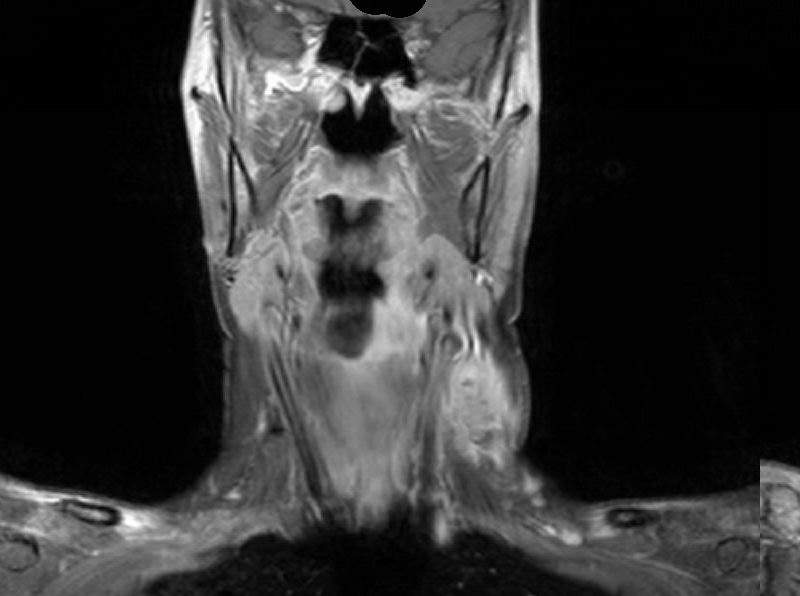

Das MRT zeigt einen Frontalschnitt eines Hypopharynx-Karzinoms mit Lymphknotenmetastasen.